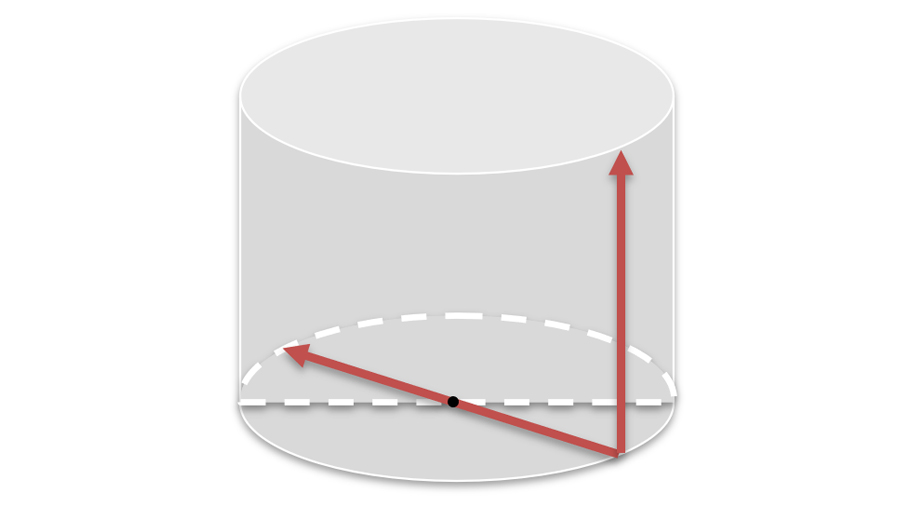

在C臂扫描过程中,始终保持拍摄主体处于射线束的中心,避免了序列图像采集过程中的横纵方向运动,减少相对运动造成的运动伪影。